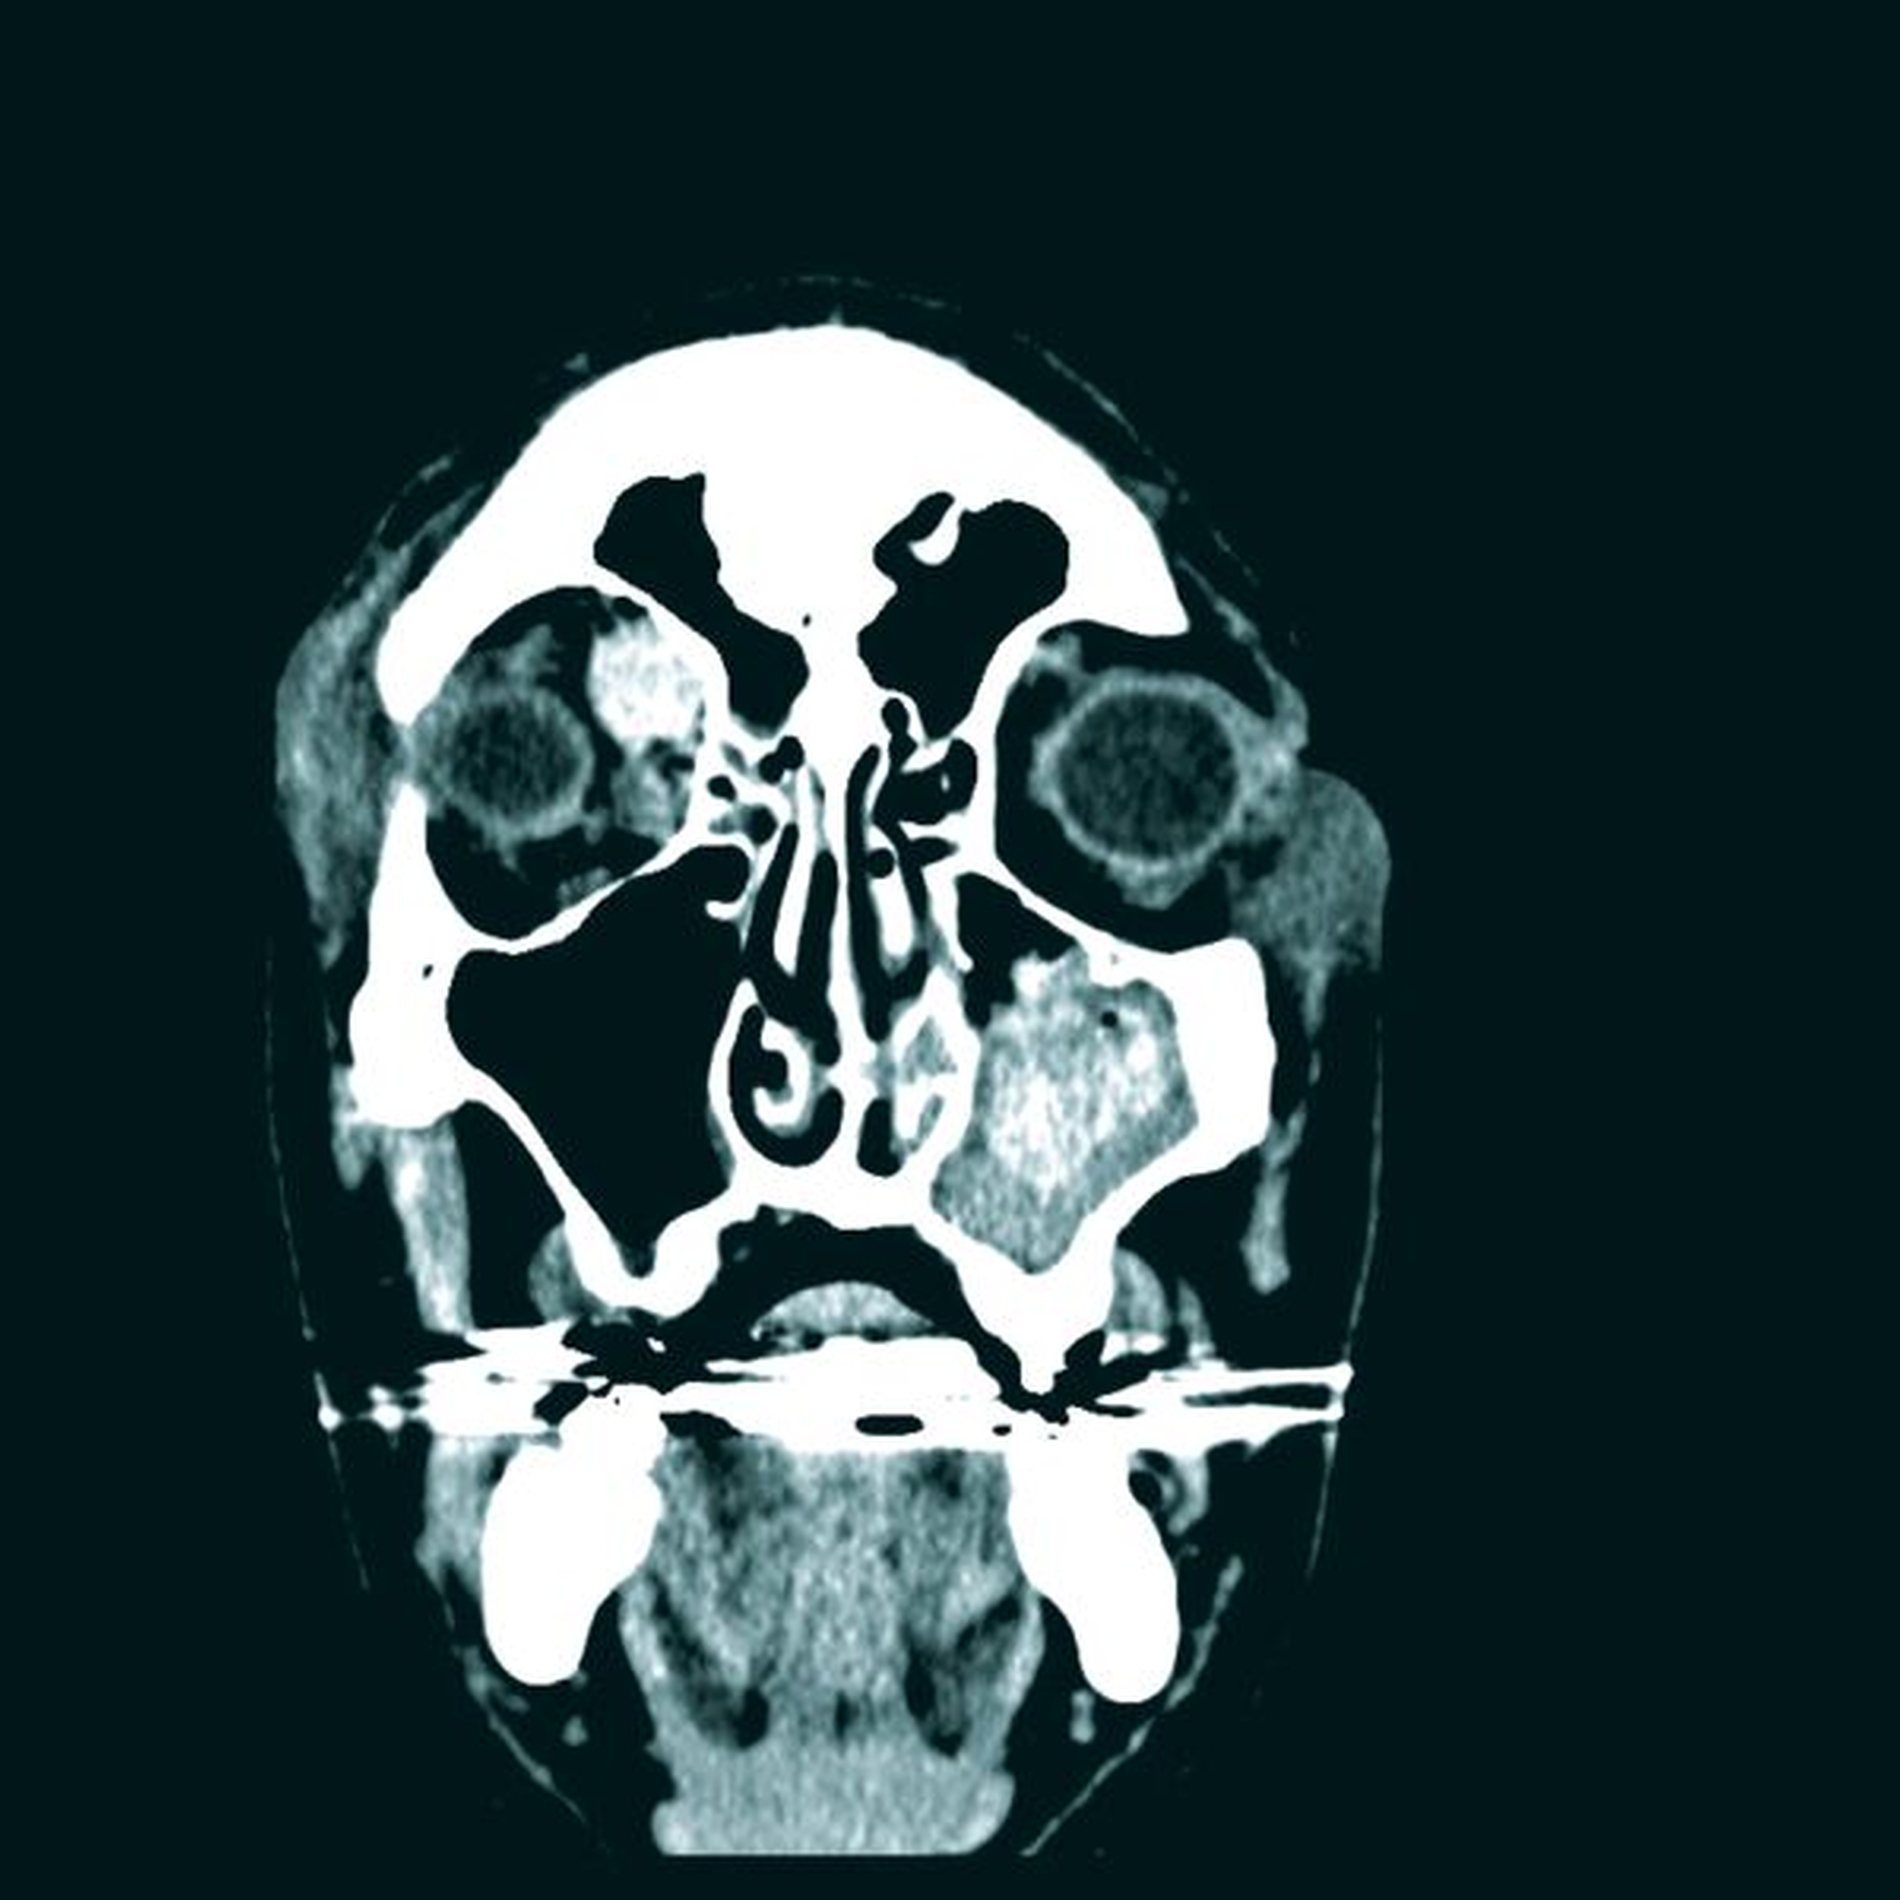

Klinisch zeigten sich am rechten Auge ein deutlich verminderter Visus bei eingeschränkter Motorik in allen Achsen mit ausgeprägtem periorbitalem Hämatom sowie ein Hyposphagma (subkonjunktivale Einblutung). Weiterhin lag eine Anisokorie vor, die rechte Pupille war weit und reagierte nicht mehr auf Lichtreize (Abbildung 1). Daher erfolgte umgehend eine CT-Untersuchung der Orbita, die eine Fraktur der rechten medialen Orbitawand am Übergang zum Orbitadach und am Bereich des Orbitatrichters an der Lamina papyracea mit Fragmentimpression in die Ethmoidalzellen nachwies. Weiterhin lag ein Hämatom von 3,3 cm x 1,4 cm an der medialen Orbitawand cranial des M. rectus medialis bis nach retrobulbär reichend vor. Dies hatte bereits zu einer Protrusio bulbi geführt. Der linke Orbitaboden war ebenfalls frakturiert (Abbildungen 2a und 2b).